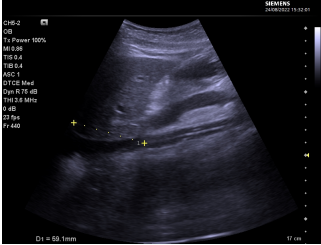

(1)插管定位:在运行过程中,除了观察管路在体外的长度,还可以通过观察流量变化、有无抖管、引流管负压变化以及患者血流动力学的变化,来确认插管的位置。此外,还可以通过床旁X线进行定位,最直观的方法是利用床旁超声或经食管超声心动图检查(TEE)进行定位。

(2)插管固定:插管定位确认后再固定,观察引流负压和局部周围软组织变化,一旦发现异常应即刻进行调整。当患者躁动时予以镇静,防止意外拔管。